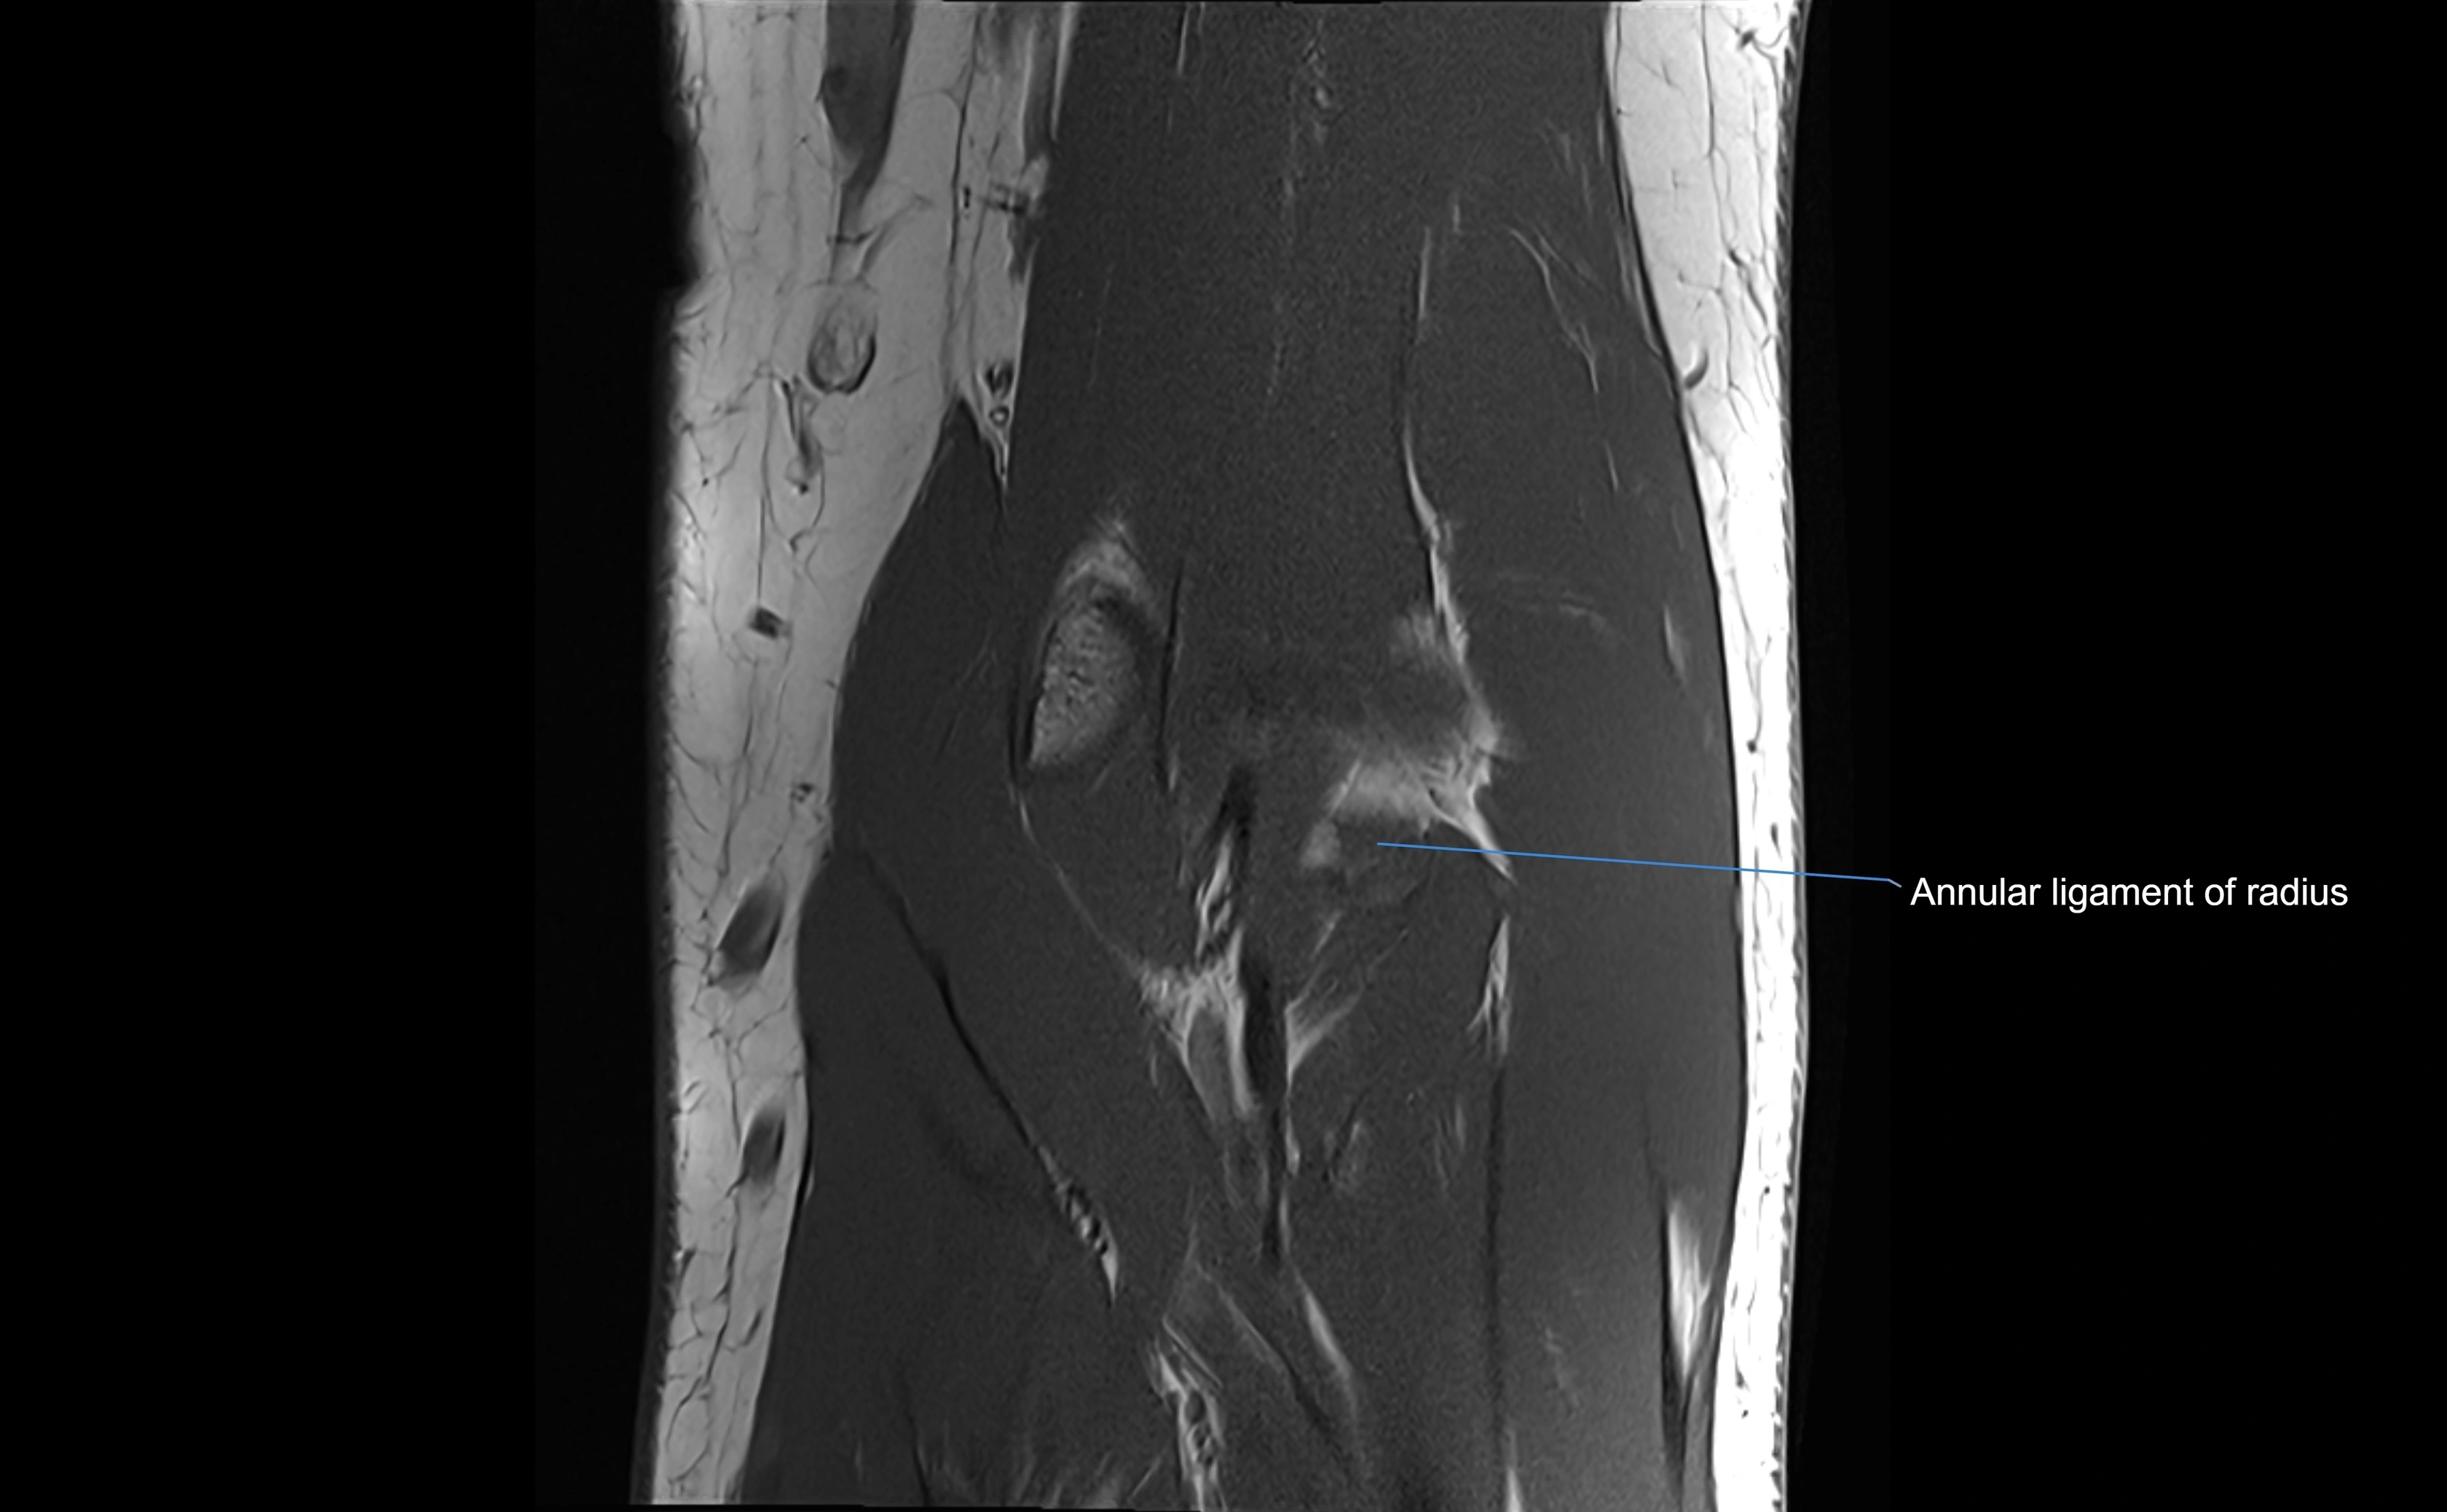

MRI Appearance

T1-weighted images:

• Ligament: low signal intensity (dark), appearing as a continuous band around the radial head.

• Adjacent fat and marrow: bright, creating contrast with the ligament.

• Thickening or disruption indicates injury or fibrosis.

• Joint capsule and synovium seen as thin low-signal lines contiguous with ligament margins.

T2-weighted images:

• Ligament: low signal (dark) with clear delineation from joint fluid.

• Fluid or edema: bright hyperintense, separating or surrounding the ligament in partial tears.

• Complete tear: discontinuity or non-visualization of ligament fibers, often with joint effusion.

MRI Arthrogram Appearance

• Contrast outlines the proximal radioulnar joint and radial head recess.

• Normal ligament appears as a dark ring surrounding the radial head, containing the injected contrast within the joint cavity.

• Partial tear: contrast extends along the ligament or beneath its fibers.

• Complete tear or subluxation: contrast extravasates around the radial head or ulna, indicating discontinuity.

• Detects capsular defects, instability, or synovial invagination with high sensitivity.